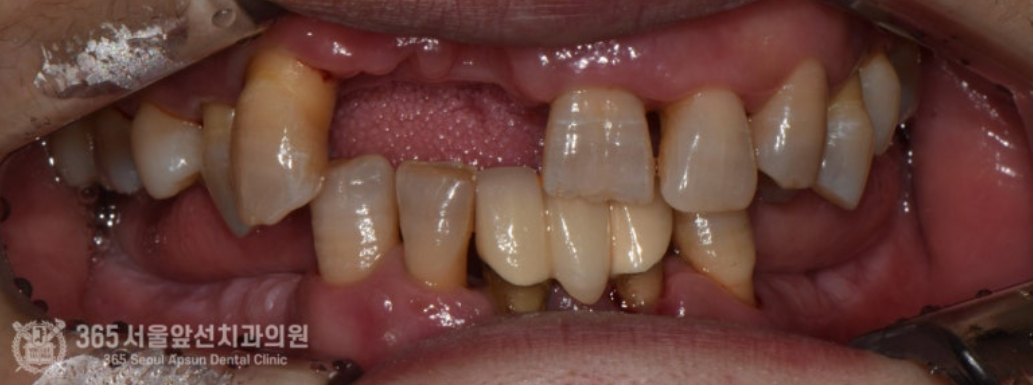

촬영일시 : 2024.08.06. 처음 내원 당시 촬영한 구강내 모습입니다. 치아가 많이 없고 남아있는 치아들 조차 상태가 좋지 않습니다. 이렇게 잇몸이 많이 부족한 경우에는, 잇몸이식을 통해 잇몸의 볼륨을 개선하고 보철물을 제작하는 것이 더 보기 좋은 보철물을 만들 수 있습니다. 촬영일시 : 2024.08.06. 오늘의 주제인 잇몸 이식을 시행했던 부위의 시행전 모습입니다. 치아가 발치되고 나면 서서히 잇몸이 줄어드는데요. 발치된지 얼마 지나지 않아서 아직은 치아가 있던 자리의 모양이 남아있는것을 보실 수 있습니다. 그러나 이 또한 시간이 흐르면 부피가 줄어들어 없어지게됩니다. 입천장에서 잇몸을 채취하여 앞니쪽에 이식을 진행했습니다.ㅎㅎ 잇몸을 입천장에서 채취해서 앞니쪽에 이식했구요~ 촬영일시 : 2024.12.01. 잇몸 이식 후 사진입니다.이식된 잇몸이 잘 생착되어가고 있습니다. 촬영일시 : 2024.12.01. 최종 보철물을 만들기 위해 임시보철물을 이용하여 잇몸 모양을 형성하고 있는 과정입니다. 잇몸이 어느 정도 안정화되면, 이후 임시보철물을 만들어서 잇몸모양을 형성해서 원하는 형태로 잡아주는 과정을 합니다. 촬영일시 : 2024.01.18. 잇몸 모양을 형성한 후, 최종적인 보철물을 제작하여 끼워드렸습니다. 촬영일시 : 2025.02.18. 아래쪽은 부분틀니를 원하셔서 부분틀니로 마무리해드렸습니다. 이번에 소개해드린 치료 증례는 잇몸 이식이라는 상당히 난이도 높은 술식을 통해 앞니의 미적 개선을 이뤄낸 증례입니다ㅎㅎ 환자분께서 매우 만족해하셔서 기쁜 마음입니다. 주안역치과 365서울앞선치과의원이었습니다. 감사합니다. [ 치료기간: 2024년 8월6일 ~ 2025년 2월 18일 ] ※ 365서울앞선치과의원의 모든 포스팅은 각 진료과 의료진이 직접 작성합니다. 365서울앞선치과의원 블로그의 임상 케이스 게시물은 환자분께 의학적으로 정확하고 상세한 정보를 드리기 위해 각 진료과 의료진이 직접 작성하며, 모든 증례 사진은 본원 의료진이 직접 시술한 증례를 촬영한 것으로, 의료법 제23조, 제56조에 의거하며 환자분의 동의를 얻어 포스팅에 사용하였습니다. 또한 해당 케이스는 본 환자분의 치료 결과이며, 환자 상태에 따라 치료의 결과는 달라질 수 있습니다. |